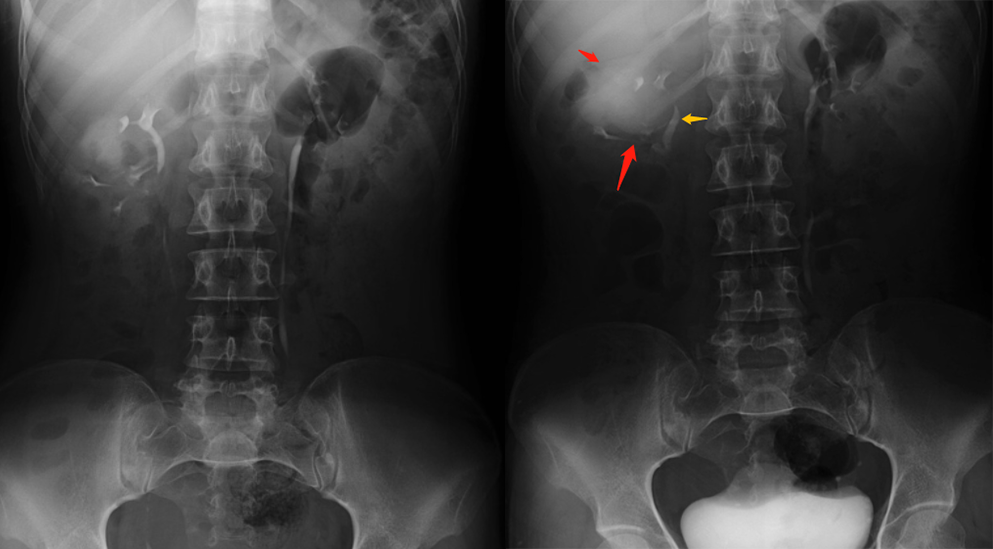

虽然超声是评估肾囊性病灶的首选检查,但大多数的肾盏憩室超声分辨不出。增强 CT 延迟期扫描在诊断肾盏憩室的敏感性为 95%,另一方面,磁共振 (MRI) 尿路水成像也成为一种有价值的检查方法,MRU 尿路造影技术,使用各种 T2 加权序列,将尿路视为静态液体柱,不需要打造影剂。

1、静脉尿路造影:表现为肾实质内圆形、边缘光滑的对比剂充盈区,有时可见与肾盏相通的细长管道。合并结石表现为囊腔内高密度影。

红色箭头所指为憩室,黄色箭头所指为肾盏。